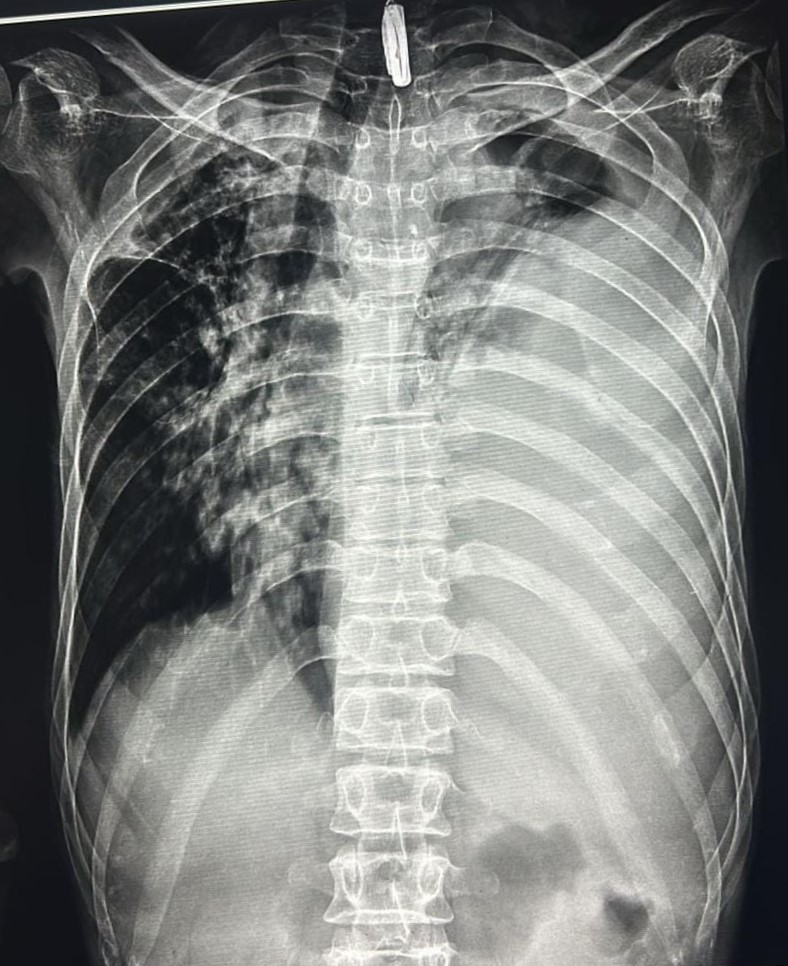

| 131 | IGGMC, Nagpur, Nagpur | P2 | 29-4341 Follow-up of 29-2136 |

Kedar Say | Consent taken on Paper | 39 Yrs. |

Provisional Diag : Left Empyema Thoracis

Final Diag : Empyema (CxR- Left Empyema With Hydropneumothorax With Left Pleural Fibrosis) |

Non-TB Case (Confirmed) | Left Hydropneumothorax With Pleural Fibrosis? | Abnormality visible on x-ray |